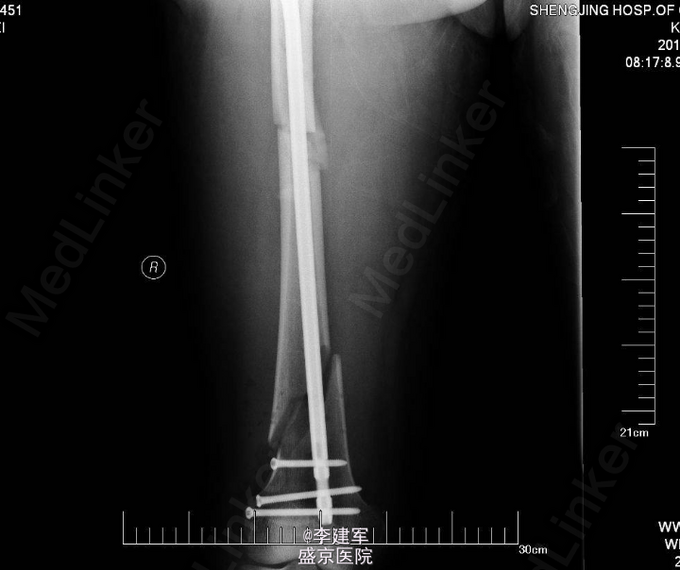

诊断:右股骨干粉碎性骨折 患者右股骨干粉碎性骨折,拟行右股骨干骨折闭合复位内固定术。

长骨的干的骨折,行髓内针闭合复位,有助于患者早期下地行走,且创口小。粉碎性骨折不破坏骨膜,骨的血运未破坏。扩髓相当于髓内植骨,有利于生长。所以本次手术行髓内针闭合复位。